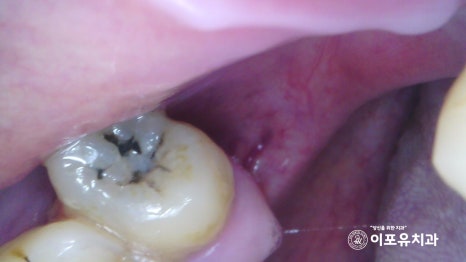

더불어 오른쪽 위 작은 어금니 한 곳에서도

심한 우식으로 인해 내부가 감염된 것을

확인할 수 있었는데요.

레진이나 보철만으로는 증상을 해결하기에

한계가 있을 것으로 판단이 들어

이곳도 함께 진료를 진행하는 것이 좋습니다.

이미 구강 내 출혈이 나타나거나

붓기와 부종이 생긴 곳들이 많았는데요.